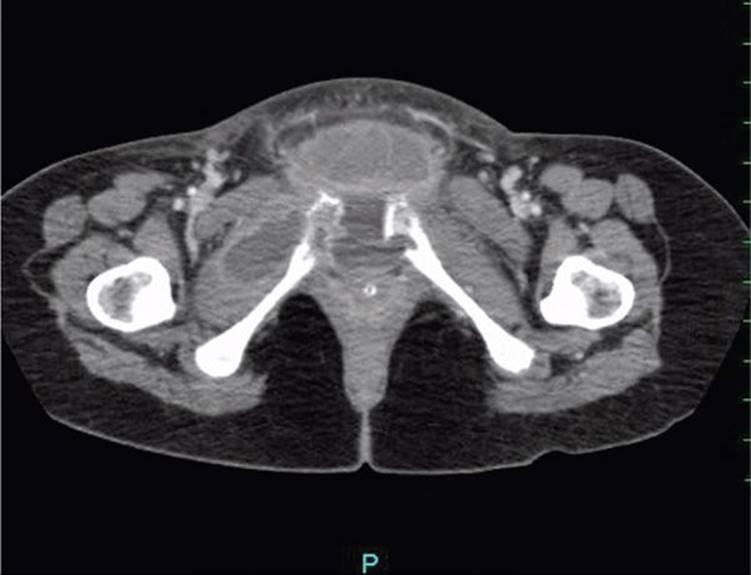

Separation of the symphysis pubis or one of the sacroiliac synchondroses during labor leads to pain and marked interference with locomotion. Estimates of the frequency of this event vary widely from 1 in 600 to 1 in 30,000 deliveries (Reis, 1932; Taylor, 1986). In our experiences, symptomatic separations are uncommon. Their onset of pain is often acute during delivery, but symptoms may manifest either antepartum or up to 48 hours postpartum (Snow, 1997). Treatment is generally conservative, with rest in a lateral decubitus position and an appropriately fitted pelvic binder. Surgery is occasionally necessary in some symphyseal separations of more than 4 cm (Kharrazi, 1997). The recurrence risk is > 50 percent in subsequent pregnancy, and Culligan and associates (2002) recommend consideration for cesarean delivery. In rare cases, fractures of the sacrum or pubic ramus are caused by even uncomplicated deliveries (Alonso-Burgos, 2007). As discussed in Chapter 58 (p. 1159), the latter are more likely with osteoporosis associated with heparin or corticosteroid therapy (Cunningham, 2005). In rare but serious cases, bacterial osteomyelitis—osteitis pubis—can be devastating (Fig. 36-7). Lawford and coworkers (2010) reported such a case that caused massive vulvar edema.

FIGURE 36-7 Bacterial osteitis pubis–osteomyelitis caused by Streptococcus milleri in a woman with symptomatic symphyseal separation.